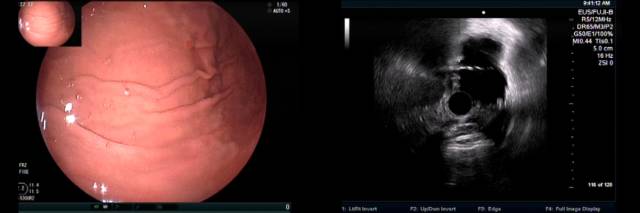

下面病例我们可以看到胃底粘膜下隆起,中央有凹陷(图A),外院CT也考虑胃底间质瘤(图B白色箭头处)。

患者拟手术来我院行超声内镜检查,小探头发现局部胃壁结构欠清,肿块内部为均匀点状回声(图 A),改环扫EUS探查见肿块后方为膈肌,内部为均匀点状回声,考虑副脾,该患者10年前因外伤切除脾脏,故诊断为脾脏切除后副脾代偿性增生外压。

嘱咐患者在我院复查CT检查,请放射科同事局部放大并重建后证实为副脾,故放弃手术。